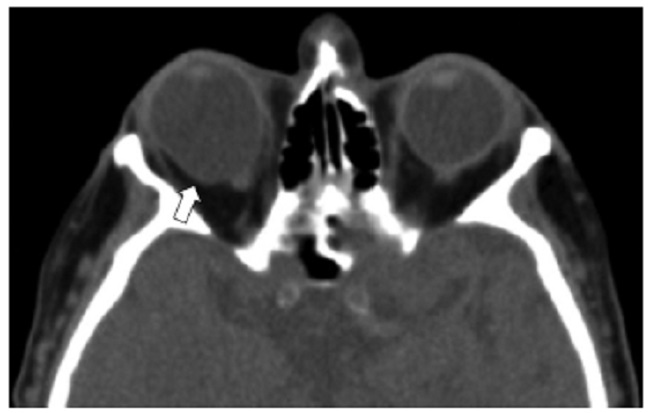

Los hallazgos tomográficos de lesión abierta del globo ocular incluyen el cambio en el contorno del ojo, pérdida obvia de volumen (llanta desinflada), la discontinuidad escleral, y el aire y los cuerpos extraños intraoculares1,6 (Figs. 2, 3, 10, 11, 12). La profundidad de la cámara anterior puede aumentar y asociarse a desplazamiento posterior del cristalino por rotura en el segmento posterior1.

Las calcificaciones oculares y el material médico se pueden confundir con cuerpos extraños u otras lesiones orbitarias1. Las localizaciones típicas de las calcificaciones permiten diferenciarlas de cuerpos extraños hiperdensos. Las más frecuentes son las calcificaciones trocleares, las placas esclerales, las drusas del nervio óptico y la ptisis bulbi. Las primeras tienen localización superomedial dentro de la órbita (Fig. 13), en la tróclea del músculo oblicuo superior, aunque se pueden observar en todas las edades, hay mayor prevalencia de calcificaciones trocleares en pacientes con enfermedades autoinmunes y niveles elevados de fosfatasas alcalinas. Las placas esclerales se localizan en los sitios de inserción de los músculos rectos medial y lateral (Fig. 14) y son más comunes en los pacientes ancianos. Las calcificaciones que ocurren cerca del disco óptico se conocen como drusas del nervio óptico (Fig. 15), las cuales se asocian a degeneración macular y pueden ser causa de pseudopapiledema benigno. La ptisis bulbi es una atrofia y calcificación del globo ocular como secuela de enfermedades infecciosas, inflamatorias o traumáticas previas (Fig. 16) (1,11. Los imitadores de lesiones abiertas del globo ocular incluyen las deformidades como coloboma, estafiloma y el globo ocular elongado por glaucoma o miopía (Fig. 17). Las masas orbitarias y los hematomas también pueden alterar el contorno del globo ocular y asociarse a calcificaciones o relacionarse con desprendimiento de retina (Fig. 18) (1,6,8,11.